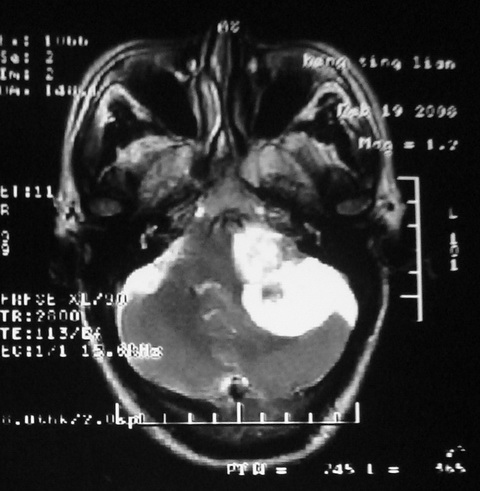

m,72,头疼,头晕两年,伴视力模糊三月,饮食呛咳两天。pe:颈部抵抗,左眼突出,左眼瞳孔约3mm,对光反射消失,双眼失明,伸舌困难,双肺呼吸音粗,心率110次/分,左上肢肌力i级,左下肢屈曲,肌张力高。现有08年2月19mri平扫及10年2月8日mri增强请会诊。ct病灶呈低密度伴散在点、片状等密度区,无明确钙化(无ct片资料可供上传)。[

脑外肿瘤,表皮样囊肿可能性大。

脑外肿瘤,囊实性,环状不规则强化,内听道扩大,考虑神经源性肿瘤

考虑表皮样囊肿。

左侧桥小脑区占位伴梗阻性脑积水----考虑 1神经鞘瘤 2室管膜瘤。

左侧桥小脑区神经鞘瘤伴梗阻性脑积水。

听神经瘤

脑外肿瘤,病灶呈匍匐蔓延,表皮样囊肿可能性大。

脑外肿瘤,病灶呈匍匐蔓延,表皮样囊肿可能性大。支持!

左侧桥脑小脑角区肿瘤并脑积水,考虑听神经瘤,脑膜瘤?

考虑听神经瘤

左侧桥脑小脑角区肿瘤并脑积水,考虑听神经瘤,